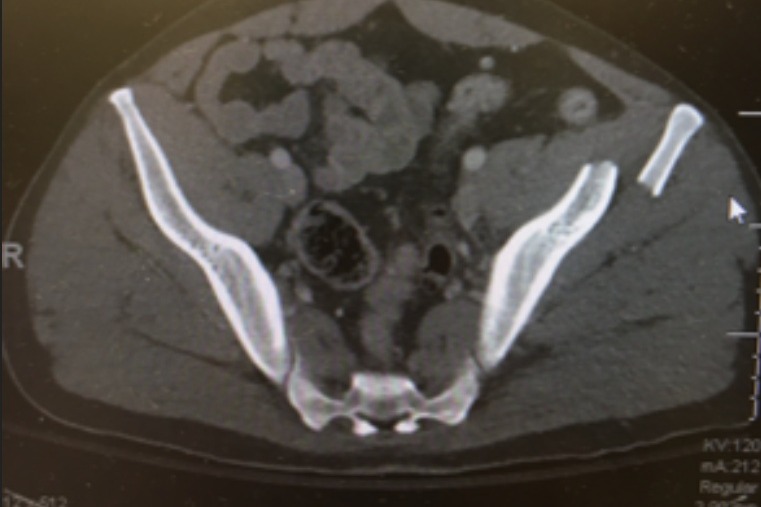

· Alex started having abdominal pain within a day or so after the surgery, which isn’t uncommon from gas build-up after surgery. But after 36 hours of intense pain and applying non-surgical measures that were not improving it, a CT scan identified that he had a perforated bowel.

· April 3rd, 2021 – Alex woke up the best he’d felt and PT even took him outside in a wheelchair so he could see Beatrice for the first time since the accident (visitors are extremely limited at the hospital). But a few hours later he started experiencing increased abdominal pain and extreme pressure yet again. A CT scan showed that he had an ileus, which is a blockage of the bowels causing the bowels to go into paralysis. They reinserted the NG tube to remove the fluid from his stomach because it was not pushing through, in order to clear the blockage and relieve pressure. This allowed the bowels to start functioning again over the course of a few days. Things continued to improve, Alex started sleeping better, he was able to start eating solid food and after a couple more days they were discussing potential discharge.

· April 18th, 2021 – An abdominal CT scan revealed that the abdominal abscess identified on March 27th has not been shrinking, despite the inserted drain, and was causing inflammation in his abdomen and likely causing the vomiting. Radiology will replace or relocate the drain, which will hopefully resolve the issue. It will take a few days to understand the impact of the procedure.